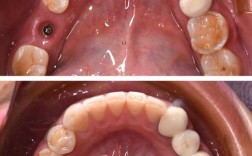

口腔卫生与咬合习惯良好

良好的口腔卫生是种植牙长期使用的保障,若患者存在未治疗的牙周炎,需先进行系统牙周治疗,控制炎症后再种牙,否则可能因炎症扩散导致种植体周围炎,最终造成种植失败,有夜磨牙、紧咬牙等不良咬合习惯的患者,需先佩戴咬合垫进行调整,避免种植体承受过大咬合力而松动。

老年人的伤口愈合能力相对较慢,术后需加强口腔卫生维护,避免种植体周围炎的发生,需定期复查(建议每3-6个月一次),检查种植体稳定性、咬合情况及牙槽骨状况,发现问题及时处理。